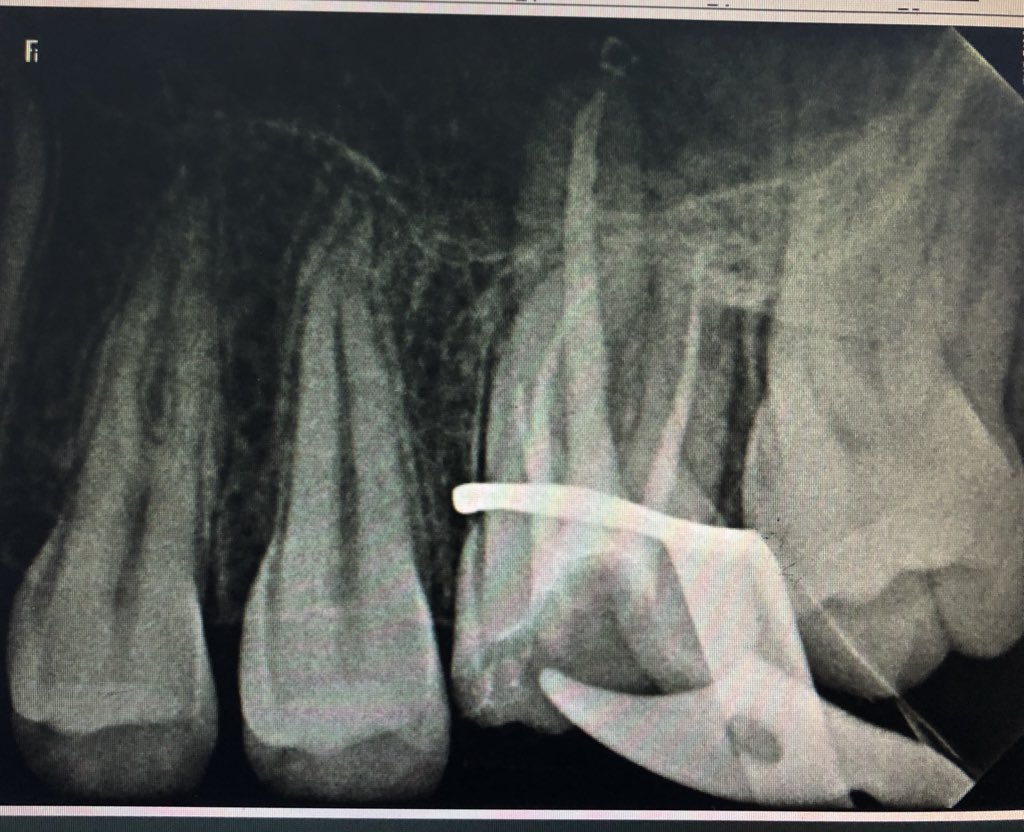

Endo Tx for upper #26 Pulpal diagnosis :necrotic pulp periapical diagnosis :SAP started at first as 3 canals by the 3rd vist Mb2 was found . Cleaning andShaping done using protapernext files #reu @RiyadhElmU_Hosp